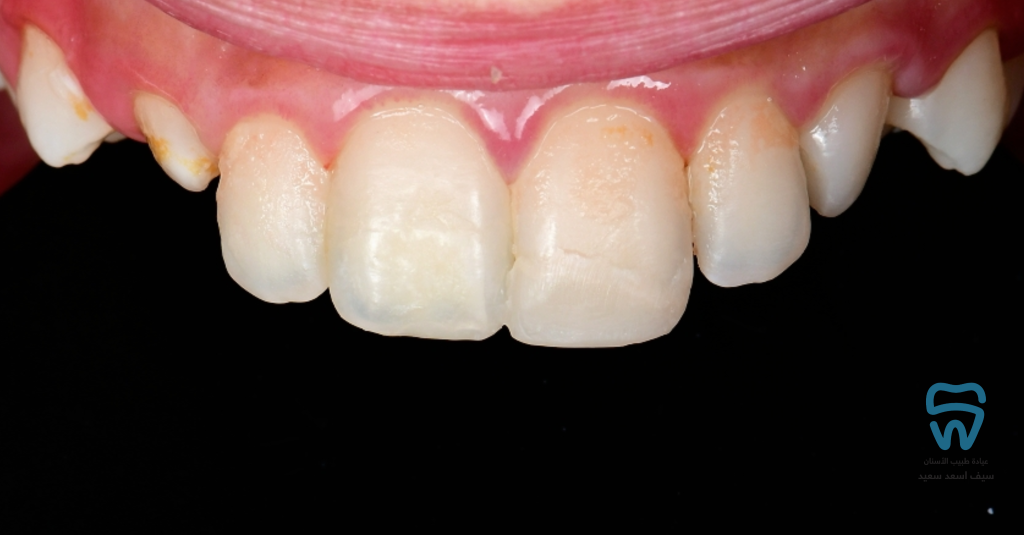

patient came with 2 fractured upper centrals

closer look at the condition

Complicated crown fracture